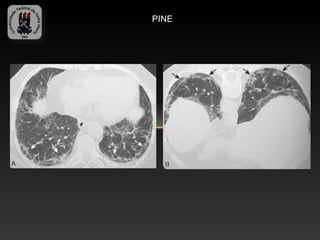

-PNEUMONIA INTERSTICIAL NÃO ESPECÍFICA

-Apresenta prognóstico mais favorável do que PIU

-Apresentação de dispnéia subaguda ou crônica com idade média de 40 –

50 anos.

- Achados TC:

-   Vidro fosco (pode se o único achado em 1/3 dos pacientes)

-   Padrão finamente reticular nas regiões inferiores dos pulmões

-   Faveolamento pode ser visto em pequena parte dos pacientes

-   Bronquiectasias ocorre com a progressão da fibrose

PINE

DPD 6- Pneumonias intersticiais idiopáticas -PNEUMONIA INTERSTICIAL NÃO ESPECÍFICA -Apresenta prognóstico mais favorável do que PIU -Apresentação de dispnéia subaguda ou crônica com idade média de 40 – 50 anos. - Achados TC: - Vidro fosco (pode se o único achado em 1/3 dos pacientes) - Padrão finamente reticular nas regiões inferiores dos pulmões - Faveolamento pode ser visto em pequena parte dos pacientes - Bronquiectasias ocorre com a progressão da fibrose